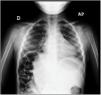

Ante la sospecha de neumonía, se realiza ecografía pulmonar (Vídeo 1), visualizando elevación diafragmática en hemitórax derecho con asas intestinales subcostales en localización hepática y pequeña condensación en lóbulo medio (figs. 1 y 2). Radiológicamente la imagen es sugestiva de síndrome de Chilaiditi (fig. 3).

Vídeo 1 Corte longitudinal a nivel de la séptima costilla. A la izquierda de la imagen vemos un patrón de líneasA de normalidad pulmonar; en el centro, el signo del telón, y a la derecha (lo que corresponde a la parte inferior del cuerpo), artefacto de reverberación similar a líneasA. No se identifica la pleura, y esto nos indica que estamos en la cavidad abdominal en el lugar en el que habitualmente deberíamos encontrar el hígado. Esto nos tiene que sugerir un síndrome de Chilaiditi, en el cual las asas intestinales se interponen entre el diafragma y el hígado, desplazándolo.